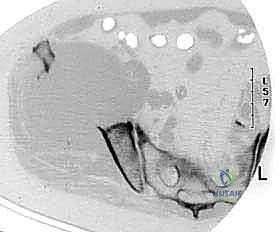

| التصوير المقطعي (CT Scan) | تقييم الهيكل العظمي بدقة ثلاثية الأبعاد. | دقة عالية جداً. أساسي للتخطيط الجراحي وقياس حجم التآكل العظمي. |

| الرنين المغناطيسي (MRI) | تقييم الأنسجة الرخوة، نخاع العظم، والحبل الشوكي. | ممتاز للكشف المبكر جداً ولتحديد مدى انضغاط الأعصاب الشوكية. |

| المسح الذري للعظام (Bone Scan) | فحص الهيكل العظمي بالكامل للبحث عن نقائل متعددة. | حساس جداً لاكتشاف أماكن النقائل في كامل الجسم في وقت واحد. |